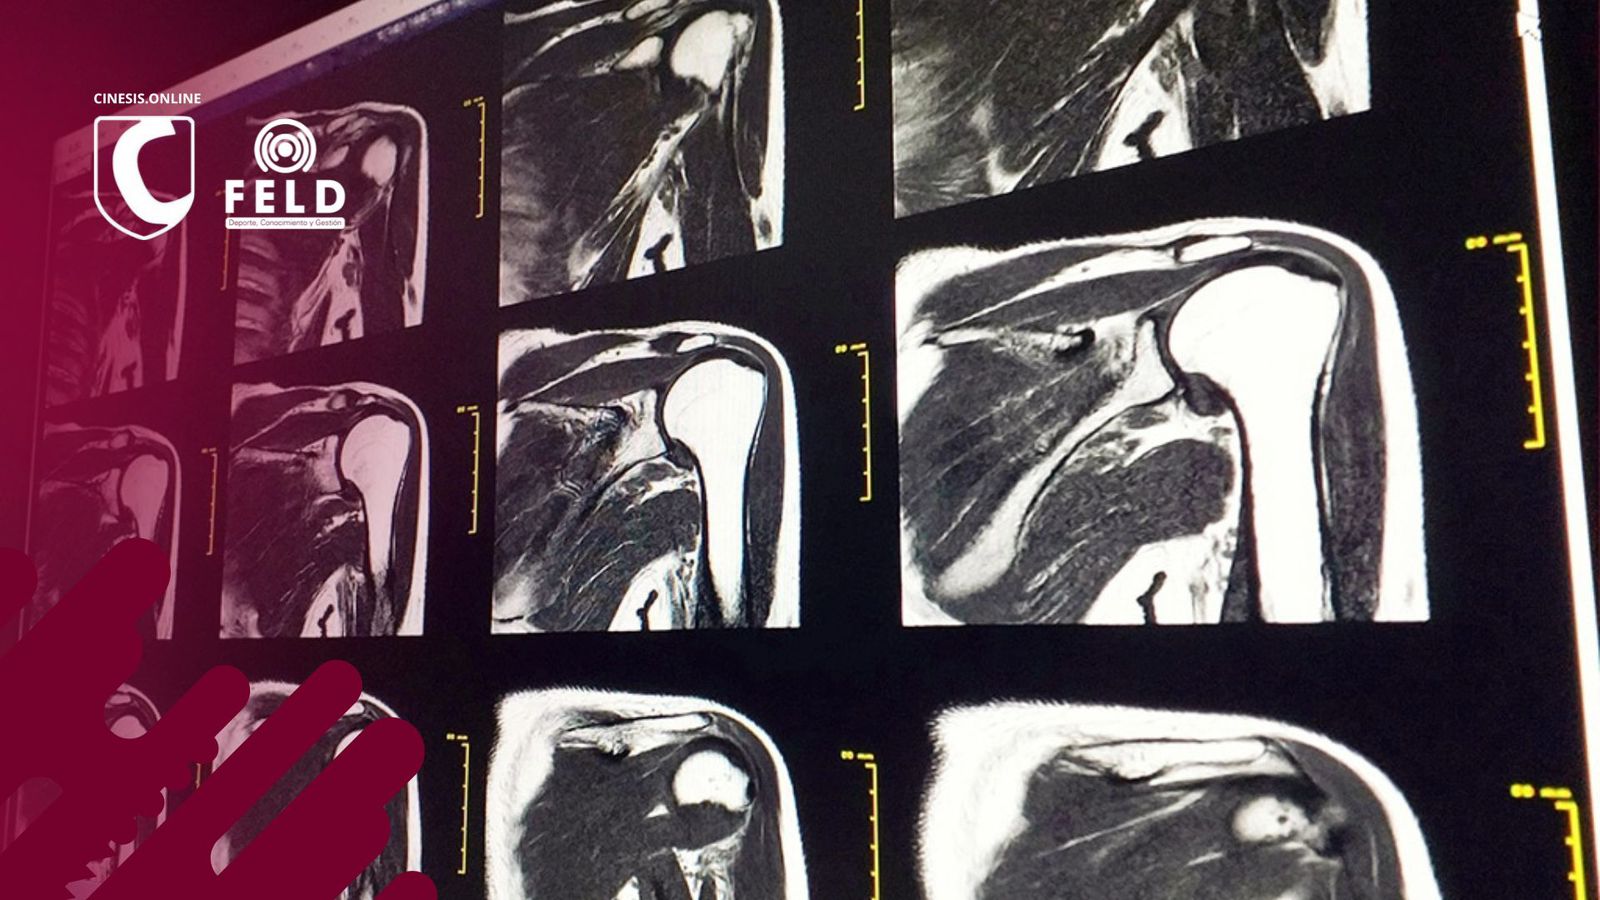

Ahora bien, ¿qué pasa cuando la resonancia o la ecografía muestran “alteraciones” que también están presentes en personas sin dolor?

En 2019, Py Barreto y colegas publicaron un trabajo en el Journal of Shoulder and Elbow Surgery en el que evaluaron resonancias bilaterales en pacientes que tenían dolor en un solo hombro. El hallazgo fue contundente:

- La mayoría de las “lesiones” aparecían también en el hombro sano.

- Tendinopatías, cambios en la articulación acromioclavicular, líquido subacromial y lesiones labrales eran igual de frecuentes en hombros con dolor y sin dolor.

- Solo los desgarros completos del supraespinoso y la artrosis glenohumeral mostraron mayor prevalencia en los hombros sintomáticos… aunque otros estudios también describen estos hallazgos en personas sin síntomas.

En resumen: muchas veces la resonancia no explica el dolor del paciente.